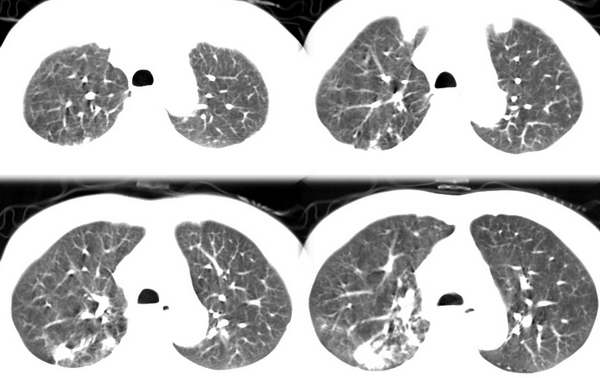

咳嗽6月低热1月!

右上肺和左下肺见有斑片状及条片状影,边缘模糊,纵隔内无肿大淋巴结,结合病史考虑肺结核可能大。

两肺纹理增粗,右上和左下肺可见肿块影,呈空泡征,分叶征。纵隔内无肿大淋巴结。考虑为肺瘤可能性大。

右上叶背段及左下叶见斑片状密度不均模糊影,右中叶支气管狭窄,中叶密度增高,体积缩小.纵隔未见明确淋巴结.结论:1、两俩结核,右中叶支气管内膜结核,并中叶肺不张。2、两肺炎;右中心型肺癌,并阻塞性肺不张。

右肺上叶尖后段及左肺舌叶 下叶见斑片状密度不均模糊影,右中叶支气管狭窄,中叶密度增高,体积缩小.纵隔未见明确淋巴结。考虑:双肺结核伴右侧中叶不张。

右上叶背段及左下叶见斑片状密度不均模糊影,右中叶支气管狭窄,近端未见肿块,中叶密度增高,体积缩小.纵隔未见明确淋巴结.结论:两肺结核,右中叶支气管内膜结核,并中叶肺不张。肺纹理粗乱,有慢支表现,伴有感染存在。

ct显示病灶呈多灶性分布,主要分布在双肺上叶后段,右肺中叶及左肺下叶,右肺上病灶内可见点状钙化,纵隔内示淋巴结钙化,结合病史6个月伴低热,考虑感染性病变,结核可能大.